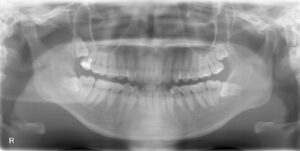

共に、画面向かって左下一番奥の親知らずの抜歯です。

2人とも歯茎の下に完全に埋まっておりました。